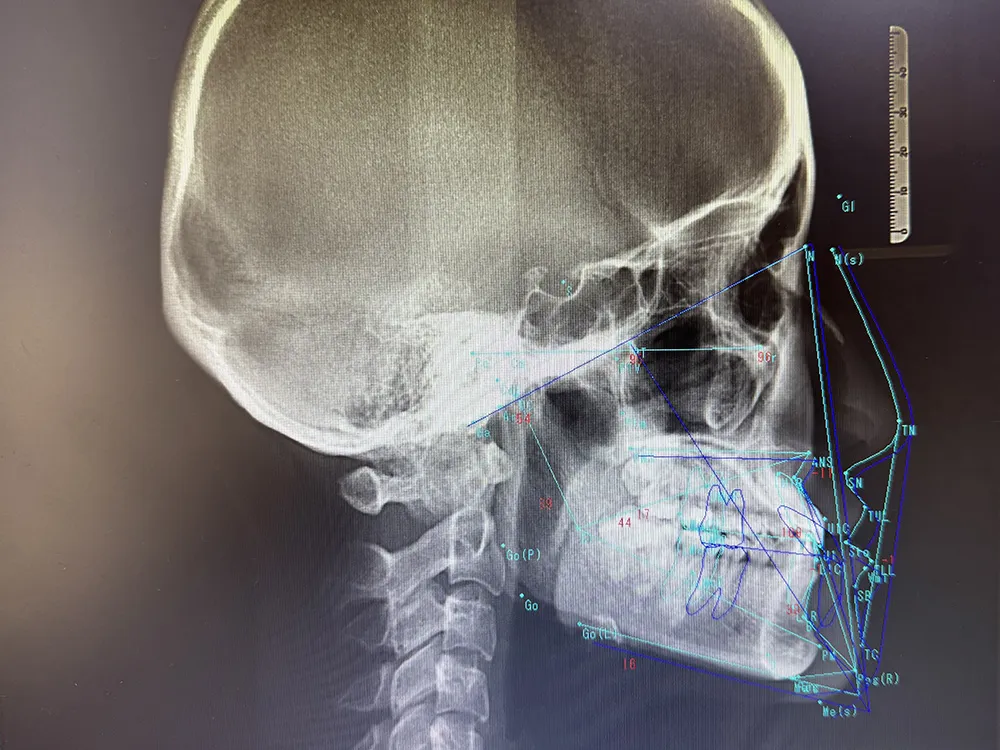

治療前のシミュレーションを徹底

全てのスタッフが治療前に十分なシミュレーションを行い、それぞれのケースに応じた万全の準備で患者様の治療に臨んでいます。

レントゲン写真